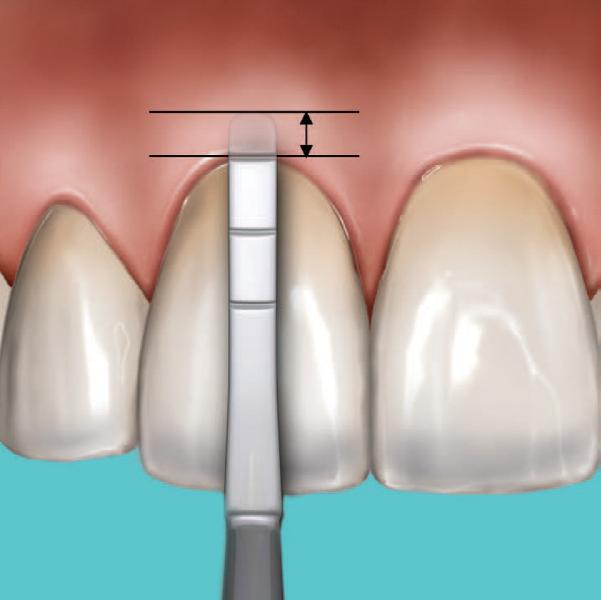

Why deep margin elevation?

Deep margin elevation will make the impression easier by moving the proximal margin of the restoration supra-gingivally, which is especially important for intra-oral scanning. It helps in avoiding periodontal surgical procedures. It makes isolation of the prepared tooth and luting of the final restoration easier.

• The height of the new margin should be slightly above the gingival margin (1mm).